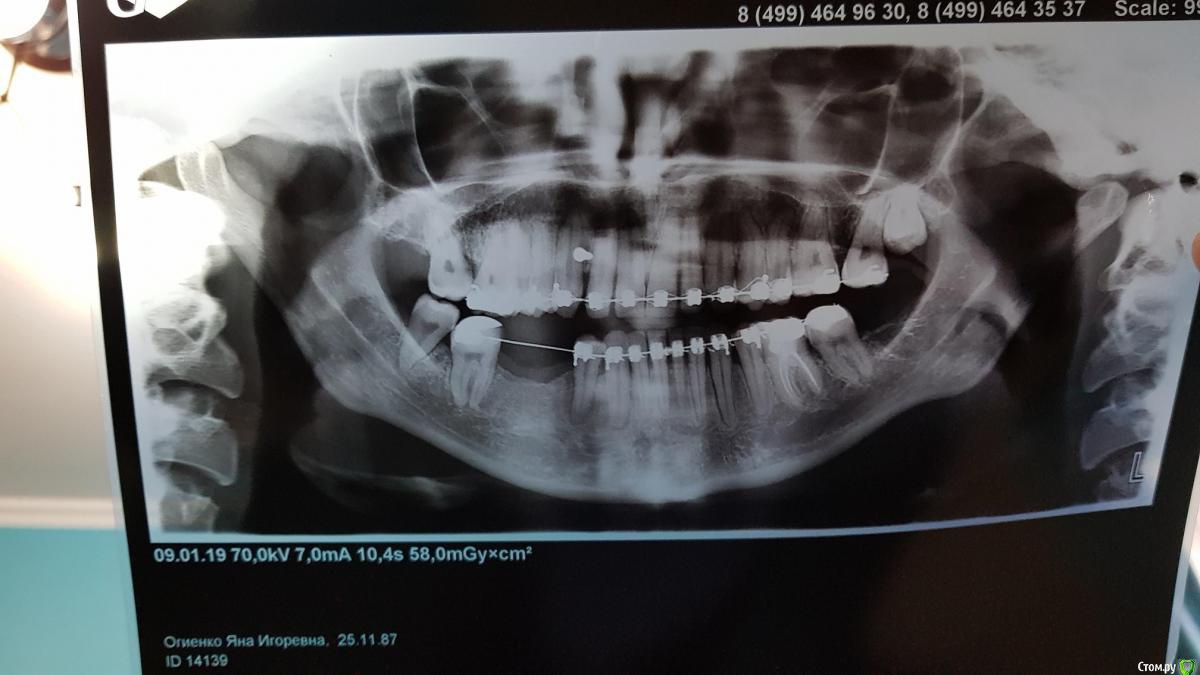

Жена начала носить брекеты в сентябре 2016 г. Цель выровнять зубы и убрать щелчки в области где суставы челюстные ( извините за термины, может и ошибаюсь) убрать щелчки при открывании рта широко.

Изначально предложили удалить сверху четверки верхние. Снизу 4 или 5 не выросло вообще (т.е. в нижнем ряду изначально не хватало 2 зубов). Сейчас после всех проделанных работ ортодонтом было предложено следующее:

удалить нижнюю восьмерку с правой стороны, с левой стороны восьмерка была удалена до начала лечения. и с левой стороны предложено раздвинуть зубы 6 и 4 (или 5 неизвестно какой там 4 или 5 в итоге вырос, а какой не вырос).

С правой стороны где большой промежуток без 2 зубов, там установлено уже 2 имплантата( сделано расщепление и установлено одномоментно два имплантата)

В итоге сейчас стоит вопрос расширять ли зубы слева снизу для еще одного имплантата и удалять 8 или же этого всего не делать, обратно стянуть и снимать брекеты.